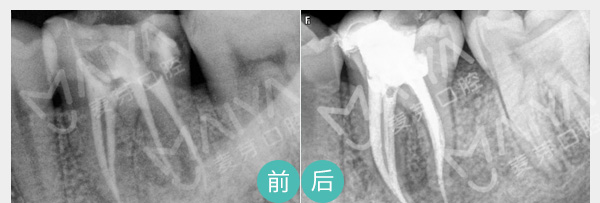

牙根疼痛、深度龋齿

麦芽显微根管治疗